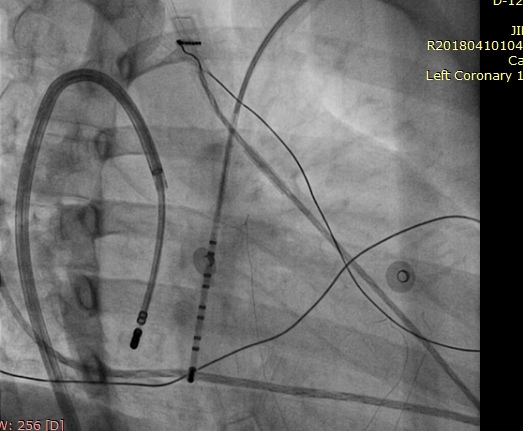

Azygous continuation of IVC

azygous1.png

RB Vidhyakar .. Raja Selvaraj. Ablation of atrioventricular nodal reentrant tachycardia using the superior approach in a patient with IVC interruption. Journal of Cardiovascular Electrophysiology 2012;23(12):1393-4

azygous2.jpg